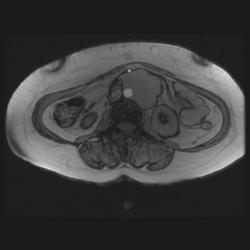

Женщина 47 лет, в течении долгого времени страдала от головных болей. В последние несколько месяцев - прогрессирующая потеря зрения (на оба глаза).

Случай "учебный", и сложностей не должен представлять.

Presented images are corresponded for cerebral (right temporal-occipital region) neoplasia; high grade glioma is most suggested.

Глиальная опухоль.